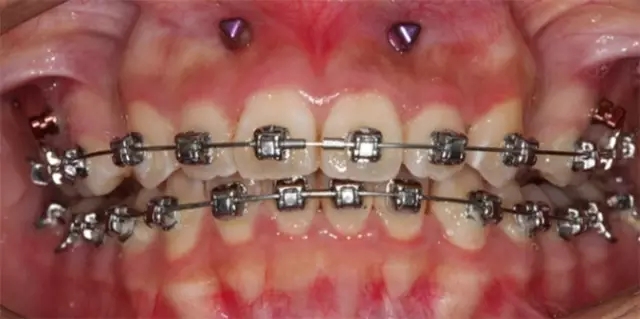

Damon 病例分享:安氏 II 類二分類露齦笑的矯治(董一磊)